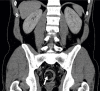

Colonic Intussusception Caused by Colonic Lipoma